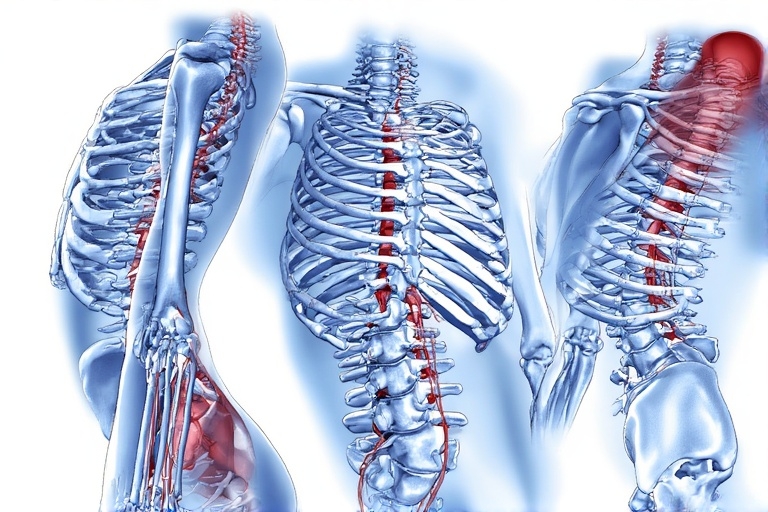

Before we dive into the exercises, let’s first understand why good blood circulation of blood flow is crucial for our physical and mental health. Blood circulation is responsible for transporting oxygen, nutrients, and hormones to various parts of the body. When blood flow circulation is poor, it can lead to a range of health issues such as chronic stress & anxiety, loss of appetite, fatigue, numbness, cold extremities, and even more serious conditions like heart disease and stroke.

Regular physical activity is one of the best ways to promote healthy blood circulation. When you exercise, your heart rate increases, pumping more blood and oxygen to your muscles and organs. This increased blood flow helps to improve the efficiency of your cardiovascular system, strengthen blood vessels, and reduce the risk of developing blood circulation-related problems.